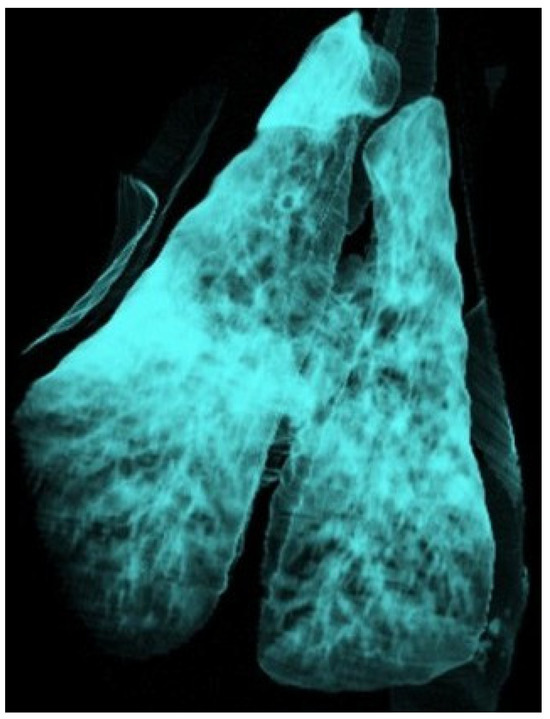

Use of Computed Tomography in the Clinical Diagnosis of Lower Respiratory Tract Diseases in Sheep

Lower airway diseases are a major health concern in sheep, often presenting with overlapping clinical signs that hinder accurate diagnosis. This study evaluated the diagnostic value of computed tomography (CT) in 58 adult sheep examined in northeastern Spain between 2017 and 2024. All [...] Read more.

Lower airway diseases are a major health concern in sheep, often presenting with overlapping clinical signs that hinder accurate diagnosis. This study evaluated the diagnostic value of computed tomography (CT) in 58 adult sheep examined in northeastern Spain between 2017 and 2024. All animals underwent full clinical examination, CT under general anaesthesia, and post-mortem investigation. CT identified 82 pulmonary lesions, including interstitial pneumonia, respiratory complex, gangrenous pneumonia, caseous lymphadenitis, parasitic pneumonia, pulmonary adenocarcinoma, and pulmonary hydatidosis. Tissue density measurements provided additional information regarding disease stage and severity. The level of agreement between CT findings and definitive diagnoses consistently exceeded that of clinical evaluation, reaching almost perfect concordance for several conditions. Moreover, CT revealed concomitant respiratory pathologies within the same animal, many of which were not detected by conventional diagnostic methods. Although thorough individual clinical examination remains essential for the correct interpretation of imaging findings and the accurate diagnosis of respiratory disorders in the field, these results demonstrate that CT provides superior diagnostic accuracy compared with standard approaches and yields valuable insights for both clinical practice and research. Despite its practical limitations, CT could represent a major advance in improving health, welfare, and productivity in sheep farming. Full article